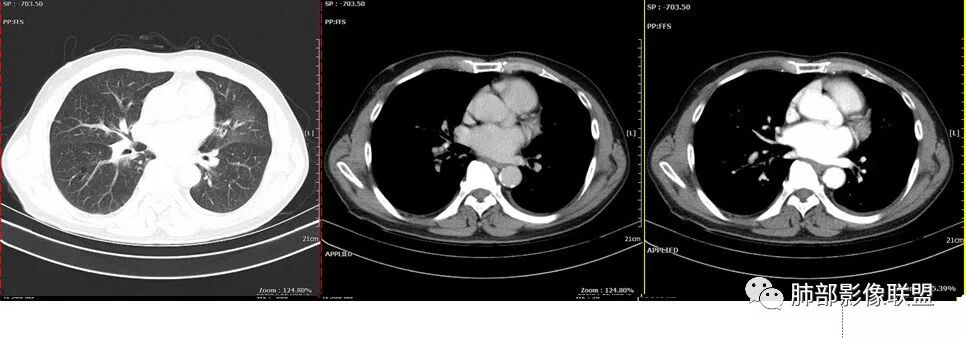

老年男性,反复咳嗽咳痰十余年,加重伴发热5天,胸痛2天。既往有糖尿病病史。白细胞不高,肝功能受损,CRP及igE明显增高。左肺上叶大片磨玻璃影伴局部实变,支气管通畅,右肺下叶背段近端支气管旁不规则实性结节,轻度均匀强化,背段支气管受压变窄,纵隔及双肺门多发淋巴结肿大并钙化。考虑左上肺感染性病变,先抗感染复查,继续查病原体。右下肺背段结节建议经TBLB活检,排外肿瘤。

患者中老年男性,发热,咳嗽5天,胸痛2天。慢性咳嗽,咳痰10余年,未目前出现活动后胸闷气短,有基础糖尿病、高血压病史,查白细胞正常,CRP增高,IGE增高,CEA轻度增高。胸部CT:左肺上叶片状密度增高影,边界清楚,内见小叶间隔增厚,呈蜂窝网格状,内有磨玻璃影,部分支气管壁增厚,部分有扩张,部分有近段粗细不均;右肺下叶可见一结节影,有凹陷,有膨隆,似有结节感。综合考虑恶性病变,腺癌可能大,鉴别结核。

患者中老年男性,发热,咳嗽5天,胸痛2天。慢性咳嗽,咳痰10余年,目前出现活动后胸闷气短,有基础糖尿病、高血压病史,查白细胞正常,CRP增高,IGE增高,CEA轻度增高。胸部CT:左肺上叶片状密度增高影,边界清楚,内血管穿行,呈蜂窝网格状,内有磨玻璃影,部分支气管壁增厚,部分有扩张,部分有近段粗细不均;右肺下叶可见一结节影,有凹陷,有膨隆,似有结节感,右侧肺门淋巴结肿大,纵隔多发淋巴结肿大、部分伴有钙化。综合考虑恶性病变,左上肺粘液腺癌可能,右下肺小细胞癌?两源论考虑:左上肺粘液腺癌或粘膜相关性淋巴瘤?右下肺结核球伴肺门淋巴结肿。

左肺上叶病灶长轴与支气管走形一致,提示沿支气管分布病变,倾向于炎性,大家可能怀疑这个病例是来源于胸膜下为主的,胸膜下来源首先整体是来源于胸膜下,与胸膜下之间没有间隙,而这例与胸膜下有间隙。而且这个病变是沿支气管朝外蔓延的,而胸膜下来源的是朝内蔓延的,唯一给我们错觉的是靠近纵隔胸膜这个地方有问题。但是靠近纵隔胸膜这个位置实变不是靠近胸膜实变,它边缘收缩的,没有膨隆的迹象。我们看到里面支气管直达远端稍扩张,是以中央间质为主、小叶间隔朝外蔓延,有间质也有实质病变,走向是沿中央间质方向走的,我个人倾向炎性病变。    问题是右下叶病灶怎么解释?右隔上、右肺门各有一个结节。这个病人有急性咳嗽、胸痛的病史,还有糖尿病病史,周围渗出比较明显,应该警惕炎性病变,要警惕克雷伯杆菌、结核、金葡菌霉菌,因为糖尿病人经常好发这些病菌感染。那么右下叶病变怎么考虑?能不能一元论?    左肺病灶是一个急性渗出为主的病变,一个急性感染的迹象;右肺下叶背段结节,没有看到支气管,增强图支气管壁增厚,局部小结节,呈分叶状,支气管堵塞,没有粘液栓样指套样改变,但是里面有强化,我倾向于癌,其次待排结核。我还是倾向于癌的可能性,恶性可能性大一些,可惜我看不到支气管腔内。还考虑有没有淀粉样变性的问题,弥漫钙化灶最常见的一个是结核,另一个是淀粉样变性。叶段支气管壁有弥漫增厚的迹象。所以淀粉样变性跟结核都要考虑。